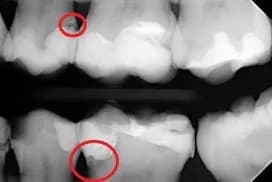

Jak odczytać próchnicę na RTG zęba i uniknąć poważnych problemów stomatologicznych

Dowiedz się, jak odczytać próchnicę na RTG zęba i uniknąć poważnych problemów stomatologicznych. Poznaj cechy próchnicy na zdjęciu RTG i zalety regularnych badań.